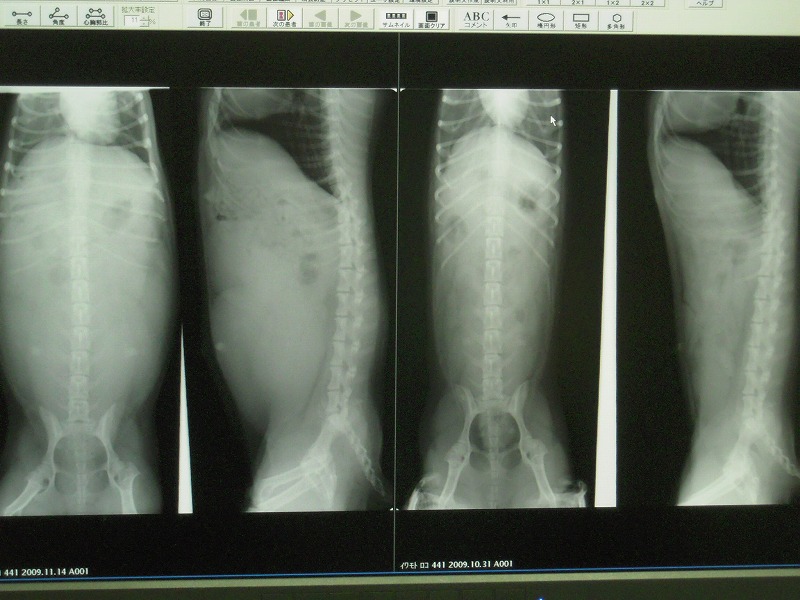

11月14日 交配から42日目 今日二回目のエコーとレントゲンをしてもらいました ![]() レントゲンには、まだ赤ちゃんはうつりませんでした。。。。。。 右の二枚が2週間前。 左の二枚が今日のです。 それぞれ 左:下から見た図。 右:横から見た図。 明らかにおなかでちょる~!(≧▽≦) 子宮が左右大きくなってて、 順調に育ってきてますね~とのこと。 犬ってひとつの子宮で2~3匹育てちゃうんだね。。 そして、 これがエコーの動画ですッ!!! *ブログになぜか貼り付かなかったので、youtubeに初upしてみましたっ 小さな背骨と、心臓がバクバク動いてるのがわかりますか?!! 右側と、左上に二匹見えてますよ。 もうコレ明らかにイキモノですよね。 ぶち、かわえぇぇぇぇぇ ![]() ![]() (半分壊れている) 次は11月28日に行ったら、何匹いるか、確実にわかるそうです! 楽しみになってきたぁぁぁぁ★ ![]() ⇒交配から48日目へ! PR |